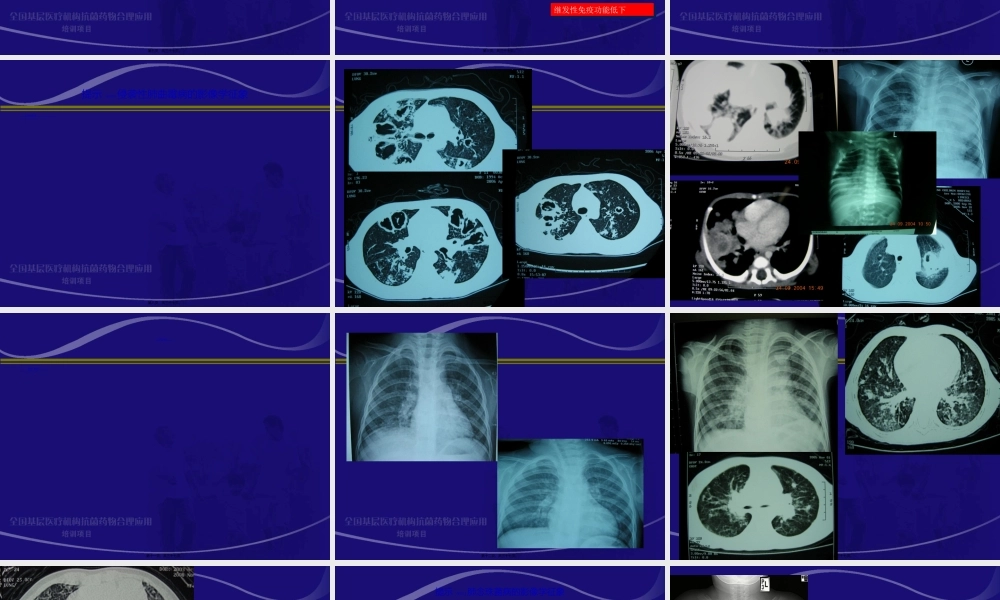

全国基层医疗机构抗菌药物合理应用培训项目(xiàngmù)儿童侵袭性肺部真菌感染的诊治赵顺英首都医科大学附属(fùshǔ)北京儿童医院第一页,共三十七页。儿童(értóng)侵袭性肺部真菌感染诊治指南中华医学会儿科学分会(fēnhuì)呼吸学组《中华儿科杂志》编辑委员会第二页,共三十七页。背景广谱抗菌药物、免疫抑制剂和抗肿瘤药物的广泛应用;各种导管的留置以及呼吸机的普及;对免疫缺陷病和真菌感染诊断水平的提高(tígāo),临床上儿童侵袭性真菌感染的患病率呈上升趋势。第三页,共三十七页。侵袭(qīnxí)性肺部真菌感染定义肺部是侵袭性真菌感染最常见(chánɡjiàn)的部位,侵袭性肺部真菌感染(InvasivePulmonaryFungalInfections,IPFIs)指真菌侵入气管支气管及肺组织引起的感染,不包括真菌寄生和过敏引起的肺部病变。第四页,共三十七页。IPFIs的诊断(zhěnduàn)IPFIs的诊断采用分级诊断模式,分为三个级别(jíbié):确诊(proven)临床诊断(probable)拟诊(possible)诊断依据:宿主(危险)因素临床证据微生物学证据组织病理学第五页,共三十七页。侵袭性肺部真菌感染诊断(zhěnduàn)—宿主因素宿主因素侵入性操作侵入性操作原发性免疫缺陷病:联合免疫缺陷病、慢性肉芽肿病原发性免疫缺陷病:联合免疫缺陷病、慢性肉芽肿病继发性免疫功能低下继发性免疫功能低下基础疾病基础疾病环境危险因素环境危险因素第六页,共三十七页。临床(línchuánɡ)证据(1)发热、咳嗽和肺部体征经抗菌药物(yàowù)治疗无好转或好转后再次出现发热、咳嗽和肺部体征。(2)影像学提示肺部病变经抗菌药物治疗无好转或肺部出现新的非原发病的浸润影。第七页,共三十七页。提示(tíshì)侵袭性肺曲霉病的影像学征象早期出现胸膜下密度(mìdù)增高的结节实变影和(或)楔形实变影、团块状阴影,病灶周围可有晕轮征(halosign);数天后肺实变区液化、坏死,出现空腔阴影或新月形空气征(air-crescentsign)。第八页,共三十七页。第九页,共三十七页。第十页,共三十七页。提示(tíshì)肺隐球菌病的影像学征象免疫功能低下儿童,多见斑片状或大片状实变,单侧或多侧,与其他病原体肺炎难以区别;免疫功能正常的儿童,多见结节(jiéjié)状阴影,单发或多发,常位于胸膜下,大小不一;弥漫性粟粒状阴影、肺间质性病变、气管支气管旁淋巴结肿大者等较少见。第十一页,共三十七页。第十二页,共三十七页。第十三页,共三十七页。第十四页,共三十七页。提示(t...

2、本站所有内容均由合作方或网友上传,本站不对文档的完整性、权威性及其观点立场正确性做任何保证或承诺!文档内容仅供研究参考,付费前请自行鉴别。

3、如文档内容存在违规,或者侵犯商业秘密、侵犯著作权等,请点击“违规举报”。